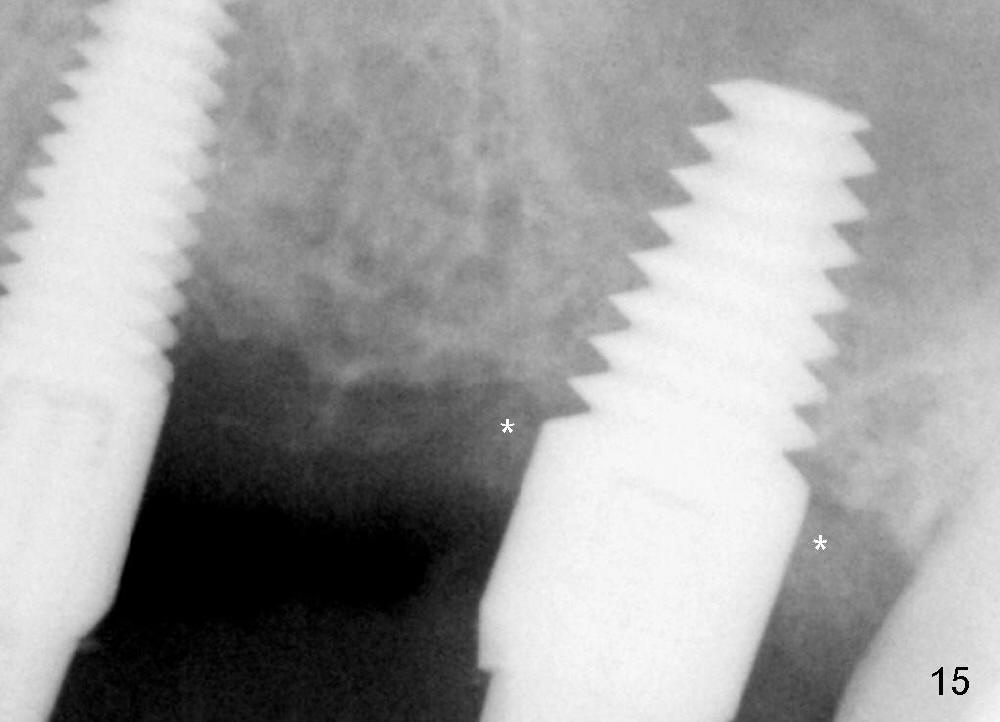

Two PAs are taken 5 months postop (Fig.15,16). Patterns of bone graft (*) between these PAs are different, which suggests presence of the graft buccal to the implant at the site of #14. Another piece of evidence of the graft is that the buccal socket heals (Fig.17 B) without implant thread exposure (Fig.19). These two implants are ready for definitive restoration (Fig.18-20). Fig.21 shows the final restoration 5 months post cementation.